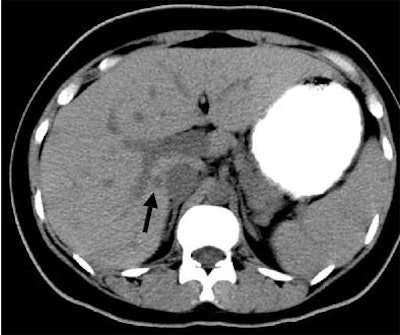

"This example of a type 4 hyperdense lesion on arterial-phase (CT) is not seen on the portal-venous phase, and the follow-up arterial-phase (scan) performed a few weeks later shows that the type 4 lesion had changed its morphology to a type 2 lesion, with a central hypodensity and peripheral hyperdense rim," he said.

| Immunocompromised patient after prolonged neutropenia with fever and candidemia. Type 4 lesion on arterial phase (above) is not seen on portal-venous phase (below). The lesion was also not visualized in arterial-phase CT performed a few weeks earlier (bottom), indicating a new lesion. |

![]() |